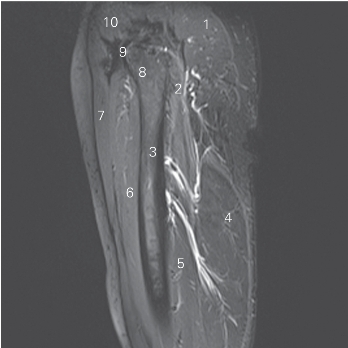

图5-14 经股骨的矢状断层的MR T1WI FS

1 臀大肌 gluteus maximus 2 股方肌 quadratus femoris

3 股骨 femur 4 半腱肌 semitendinosus

5 大收肌 adductor magnus 6 股中间肌 vastus intermedius

7 股直肌 rectus femoris 8 股骨颈 femoral neck

9 髂股韧带 iliofemoral ligament 10 臀小肌 gluteus minimus